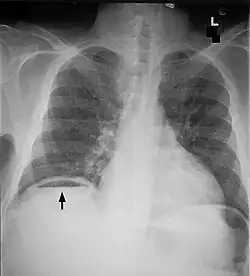

La bulle d'air visible sur l'hémidiaphragme droit (sur la gauche de l'image) est un pneumoperitoine ; vue frontale (Rayons X).